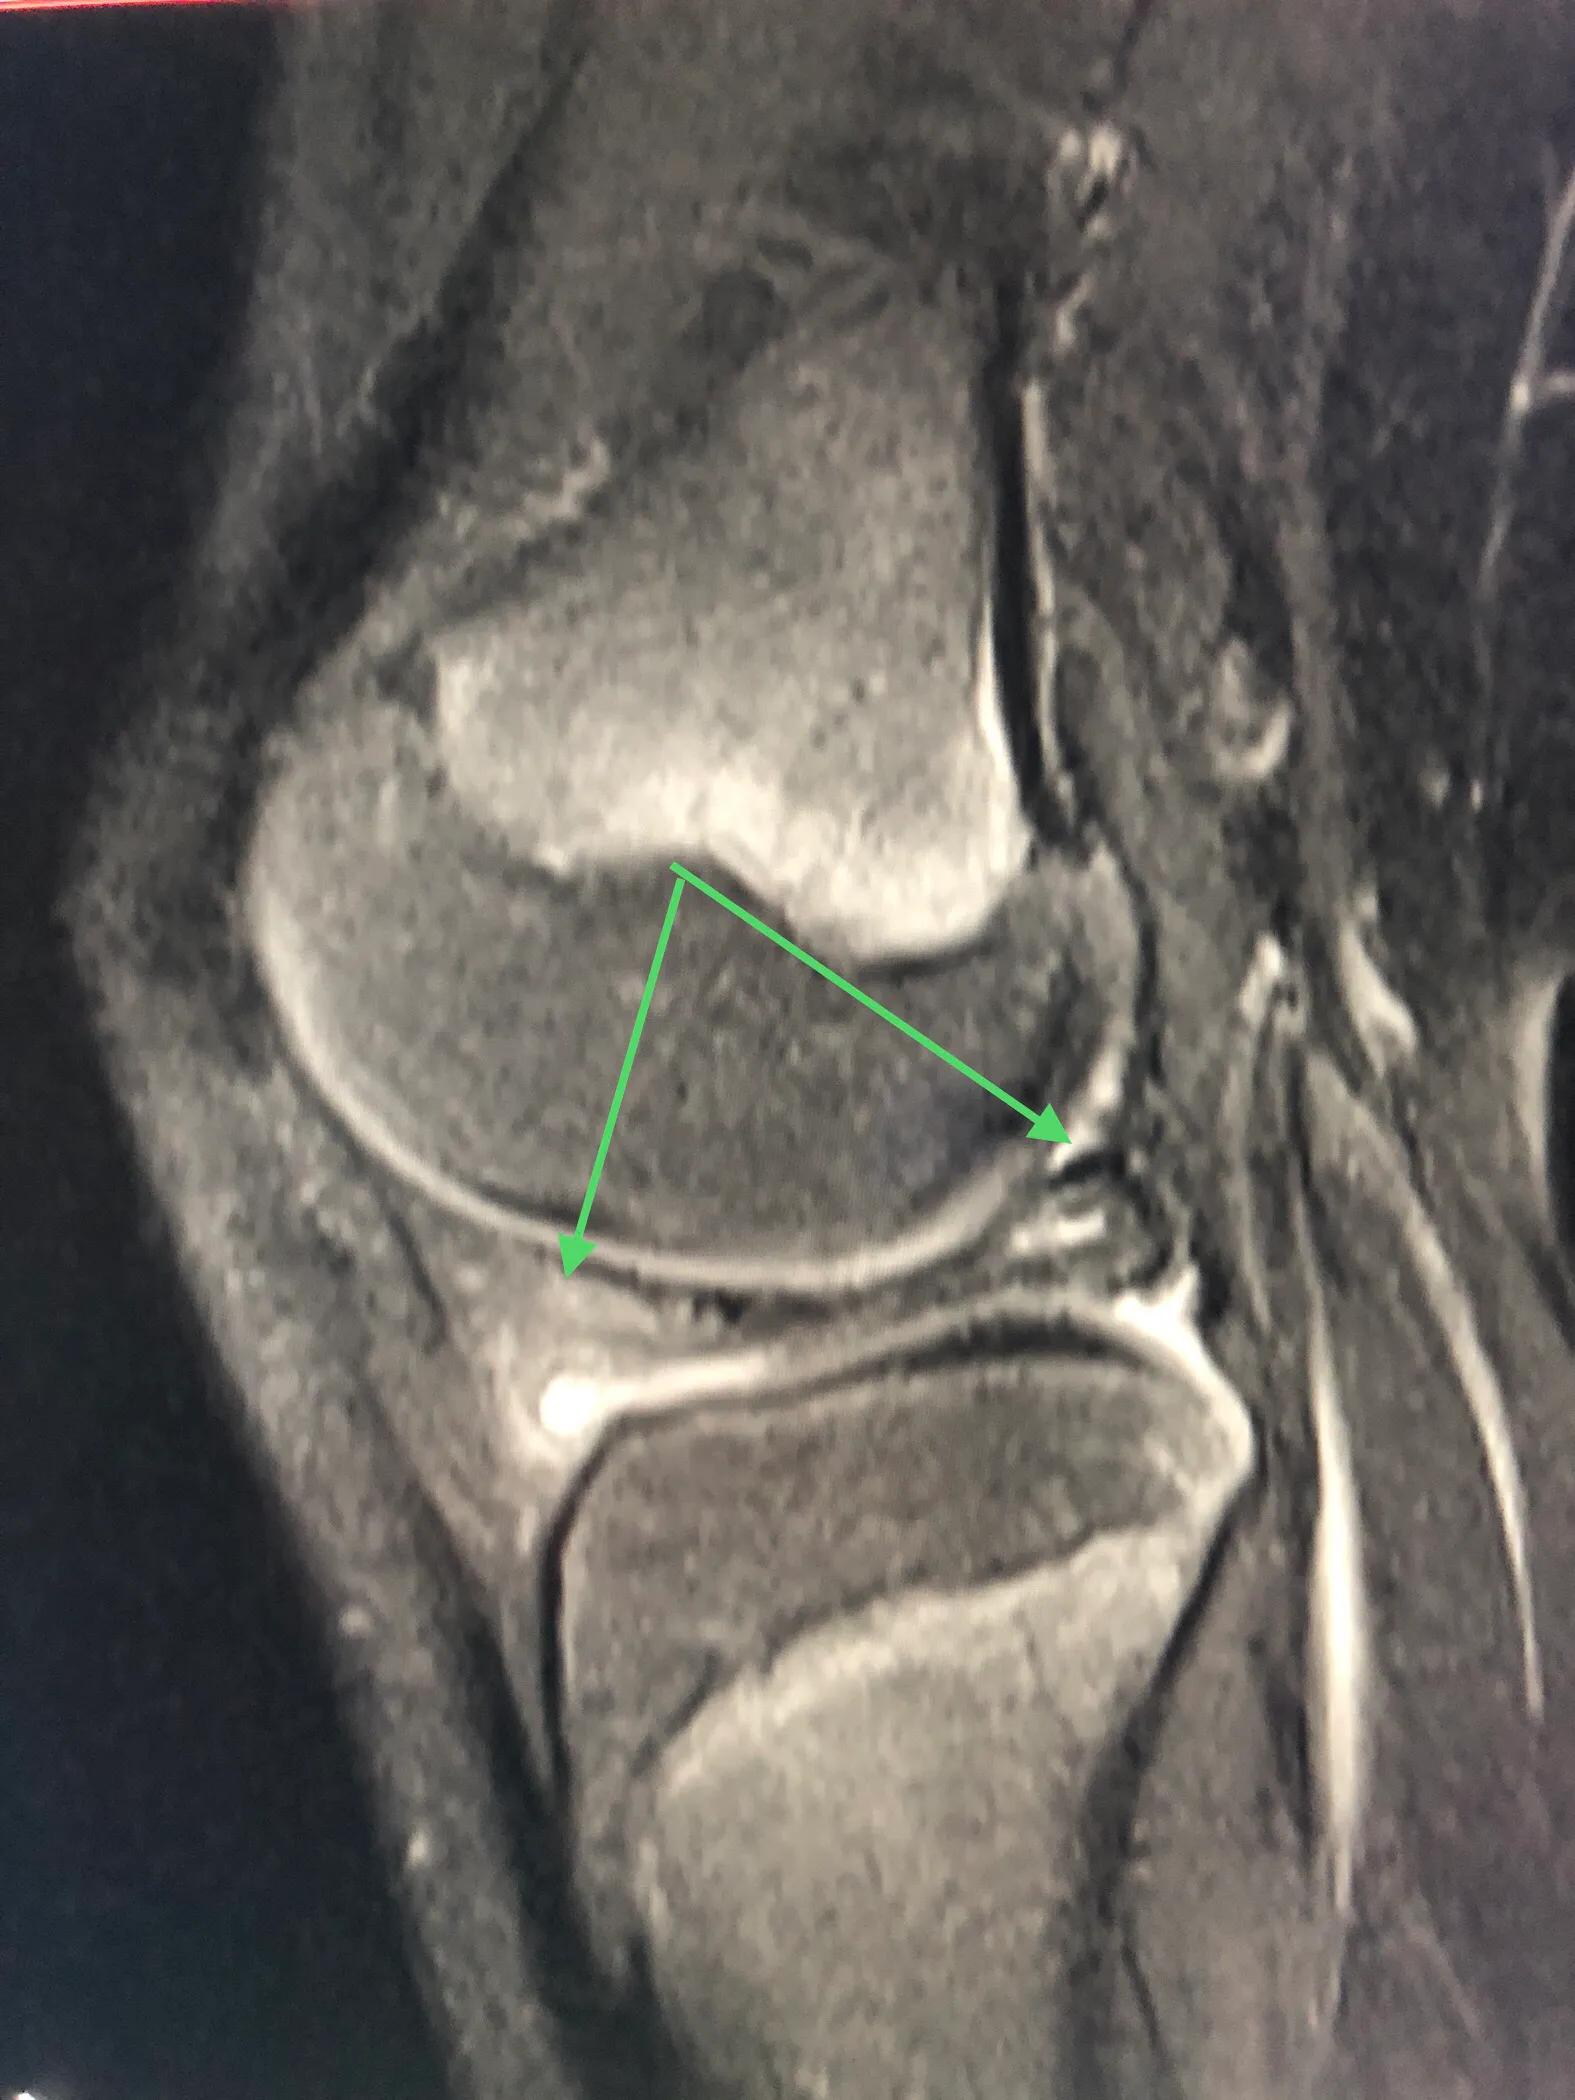

换个方向看。半月板的内侧瓣片卡压前交叉韧带,会产生弹响(右侧箭头所示)。